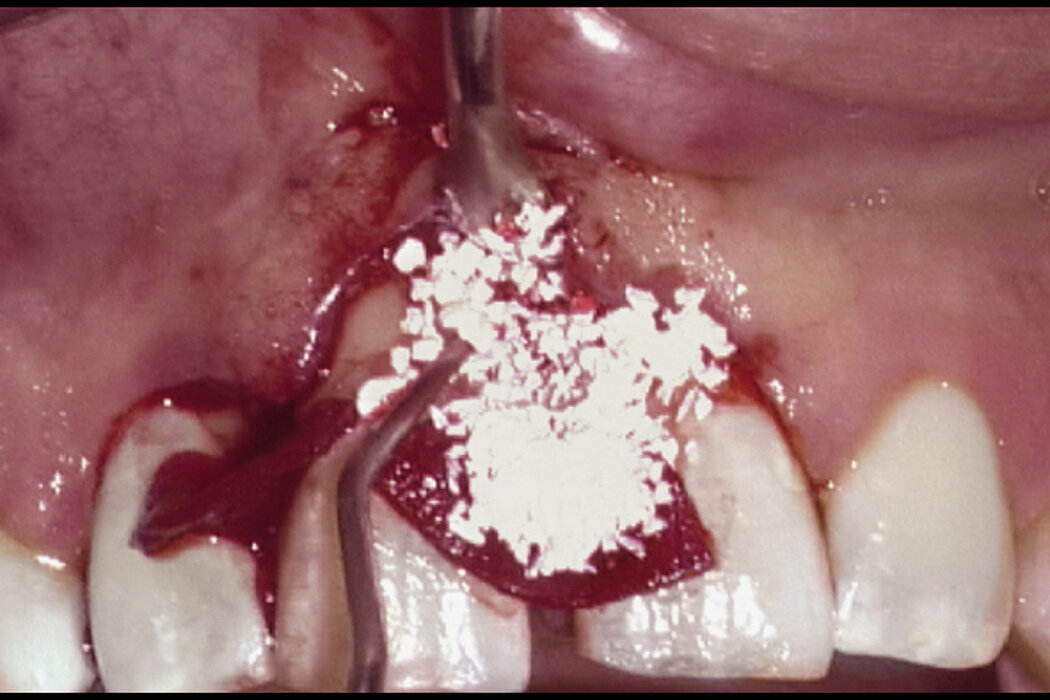

The use of biomaterials for guided tissue regeneration (GTR) is more effective than open flap debridement alone in resolving periodontal defects1. During this procedure the defect is filled with the natural bone substitute Geistlich Bio-Oss® (Collagen) and covered with the collagen membrane Geistlich Bio-Gide® (Perio).

Anterior maxillary periodontal regeneration in the aesthetic region: resolving gingival recession and preventing tooth hypermobility.

Geistlich Bio-Oss® and Geistlich Bio-Gide® Perio support re-establishment of full functional attachment.